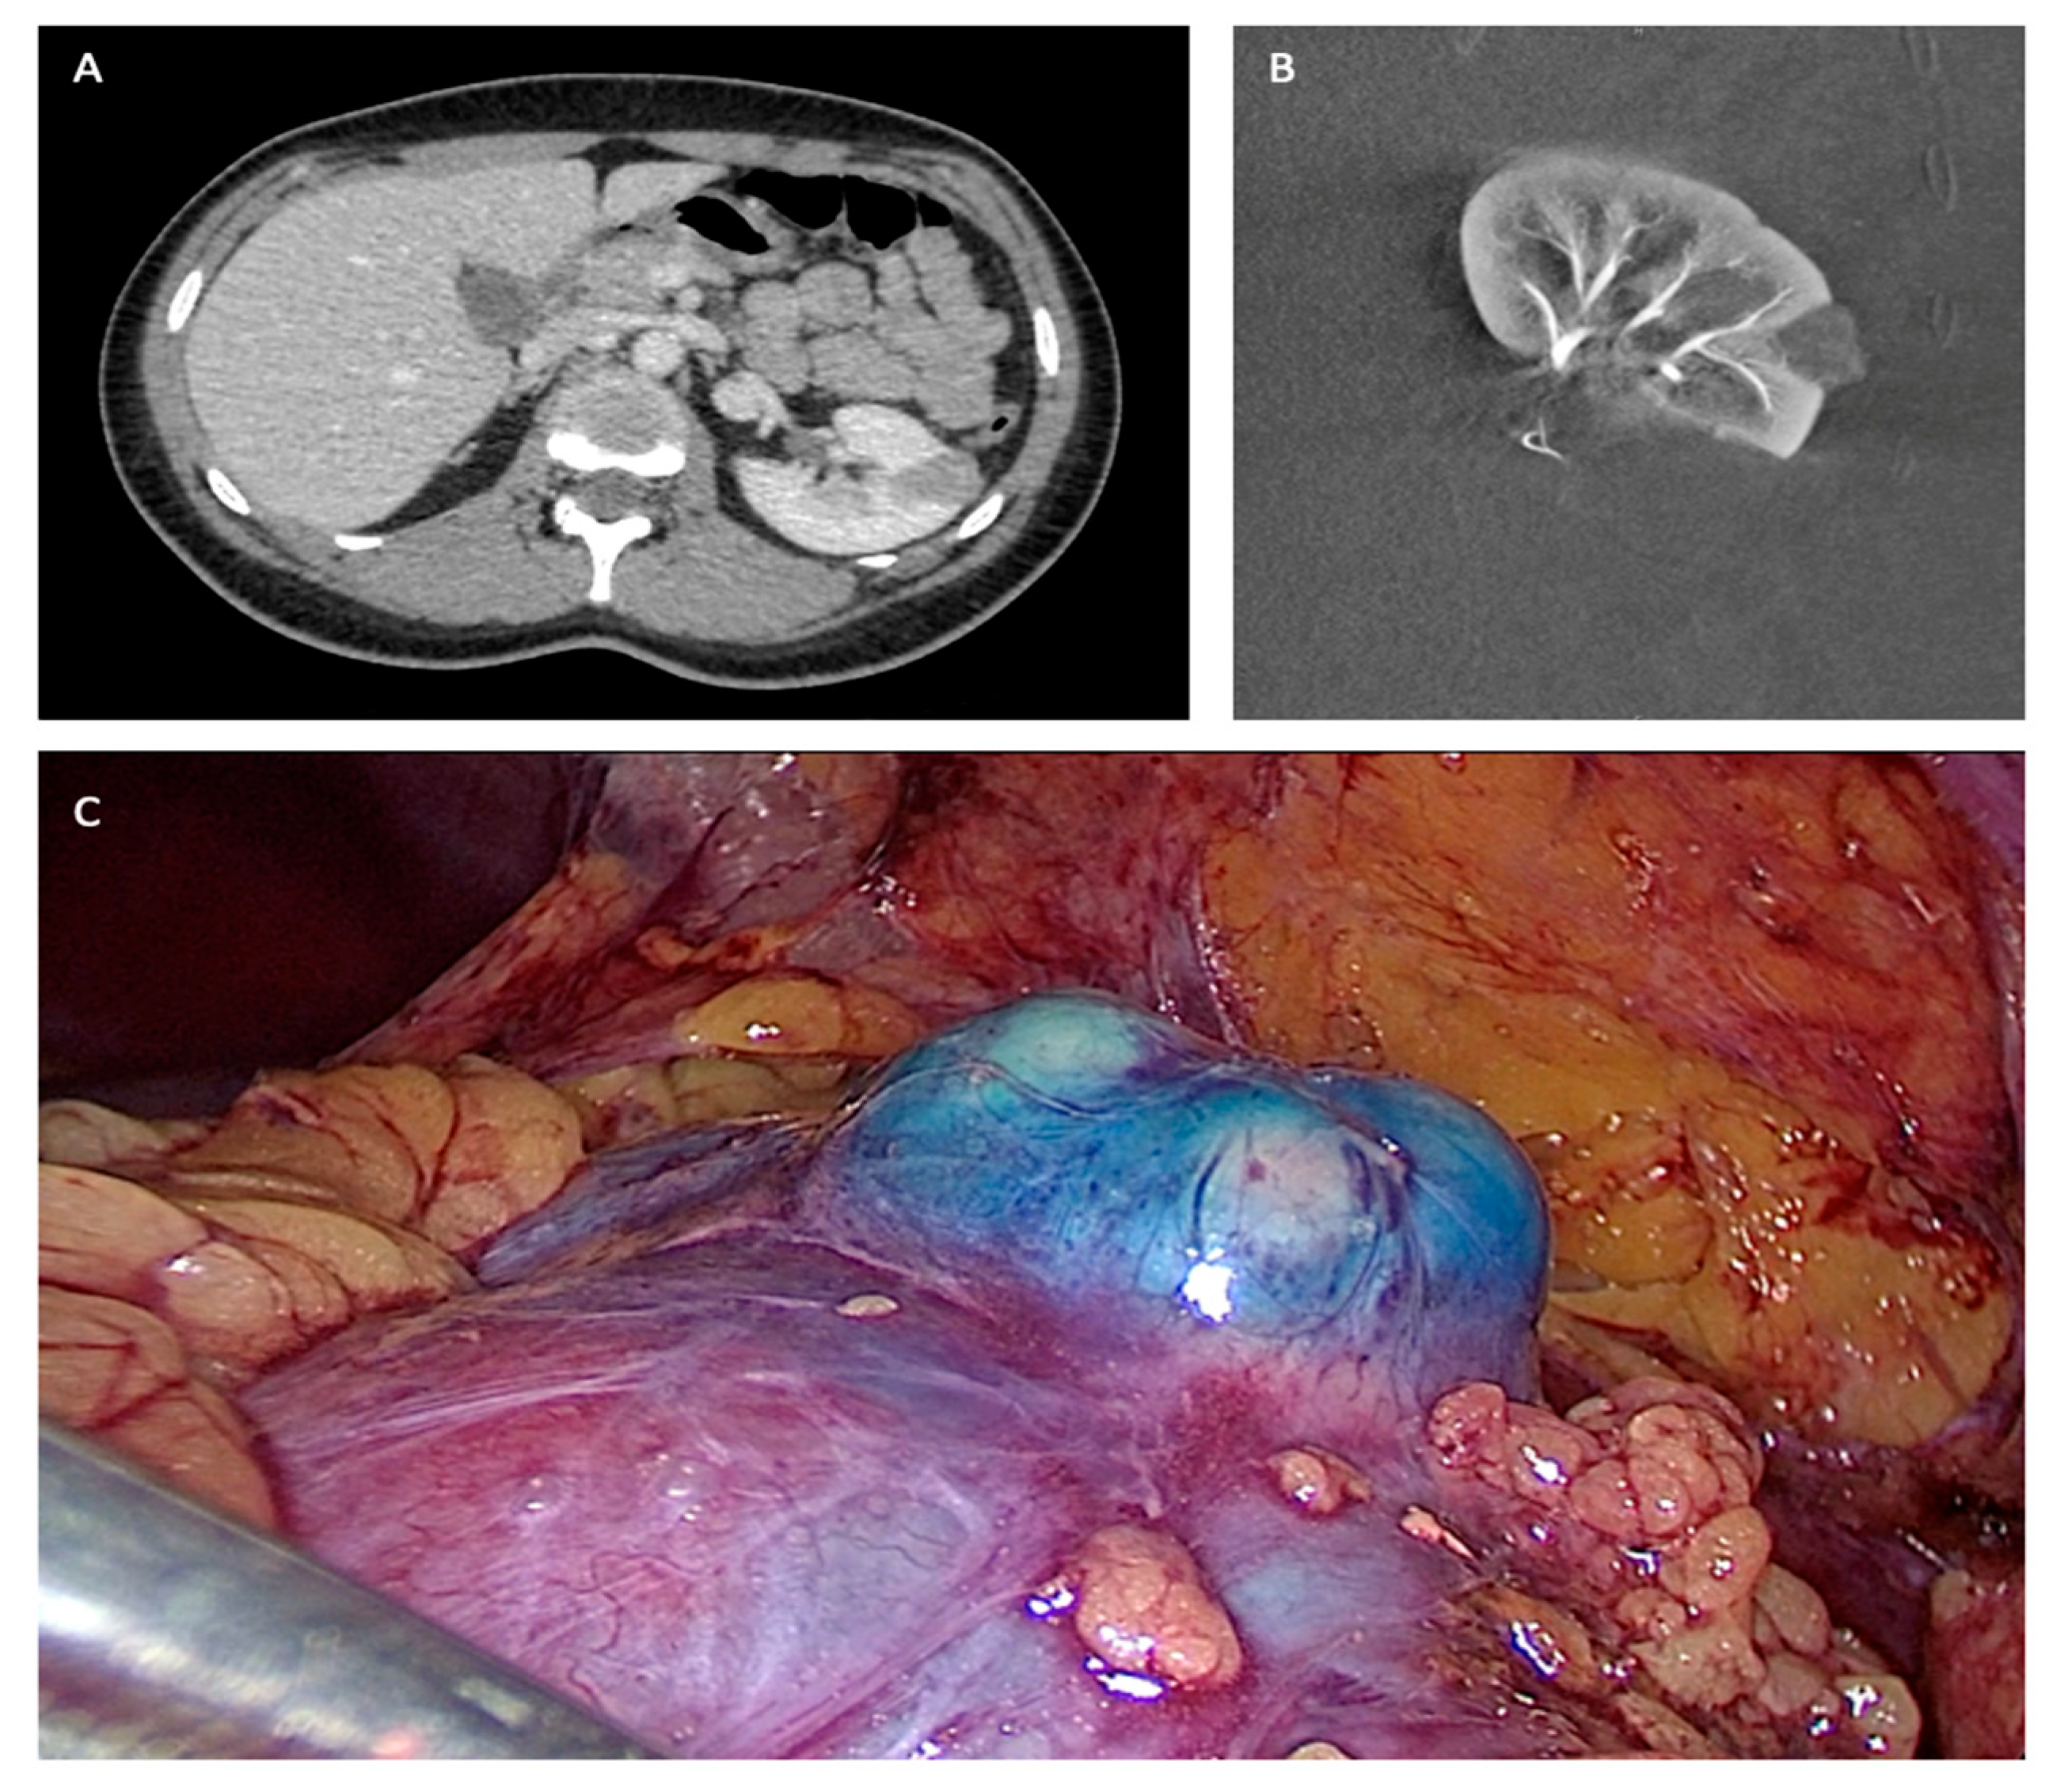

- Bouvier, A.; Besnier, L.; Paisant, A.; et al. Blue Dye Embolization of Renal Tumor: A New Technique to Improve Tumor Localization During Laparoscopic Partial Nephrectomy. J Laparoendosc Adv Surg Tech. 2020, 30, 299–303. [Google Scholar] [CrossRef]

- Bigot, P.; Bouvier, A.; Panayotopoulos, P.; Aubé, C.; Azzouzi, A.R. Partial nephrectomy after selective embolization of tumor vessels in a hybrid operating room: A new approach of zero ischemia in renal surgery: Hybrid Operating Room for Kidney Surgery. J Surg Oncol. 2016, 113, 135–137. [Google Scholar] [CrossRef]

- Panayotopoulos, P.; Bouvier, A.; Besnier, L.; et al. Laparoscopic partial nephrectomy following tumor embolization in a hybrid room. Feasibility and clinical outcomes. Surg Oncol. 2017, 26, 377–381. [Google Scholar] [CrossRef] [PubMed]